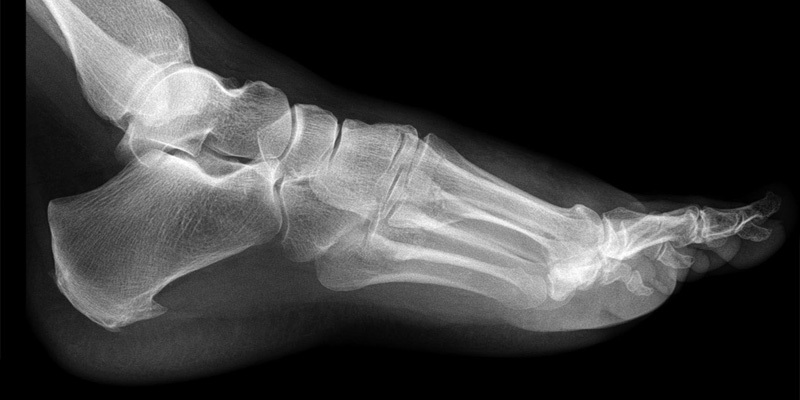

MSK (musculoskeletal) foot conditions include issues like heel pain, planter fasciitis, tendon injuries, joint pain, overuse injuries, and biomechanical problems.